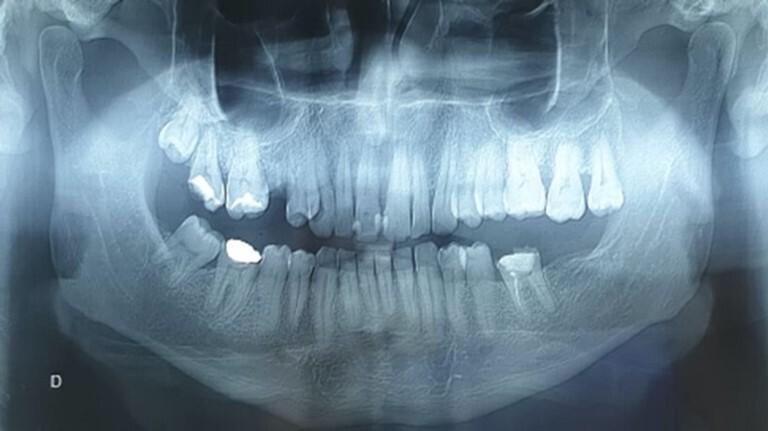

First described by J Rosai and R F Dorfman in 1969, Rosai-Dorfman disease (RDD) is a benign, self-limiting histiocytosis of unknown etiology. It is usually seen in the first two decades of life. The most frequent clinical presentation is painless, bilateral cervical lymphadenopathy accompanied by fever, weight loss, and an elevated ESR. However, RDD without nodal involvement is extremely rare, and the most common extranodal location is the head and neck region, mainly affecting the nasal cavity, pharynx, and paranasal sinuses. Oral location of RDD is occasional; according to our knowledge, only 17 cases of oral Rosai-Dorfman disease without lymph node involvement have been found in the literature. Because of the rarity of these isolated oral presentations, the clinical and radiological aspects need to be more studied. This article aims to present a rare case of oral Rosai-Dorfman disease without nodal involvement, detail the clinical and radiological signs, and the treatment strategy used in our patient.

罗萨伊-多夫曼病(RDD)于1969年由J·罗萨伊和R·F·多夫曼首次描述,是一种病因不明的良性、自限性组织细胞增多症。它通常见于生命的前二十年。最常见的临床表现是无痛性双侧颈部淋巴结病,伴有发热、体重减轻和血沉升高。然而,无淋巴结受累的RDD极为罕见,最常见的结外部位是头颈部区域,主要累及鼻腔、咽部和鼻窦。RDD发生于口腔的情况较为少见;据我们所知,文献中仅发现17例无淋巴结受累的口腔罗萨伊-多夫曼病病例。由于这些孤立的口腔表现罕见,其临床和影像学方面需要更多研究。本文旨在介绍1例罕见的无淋巴结受累的口腔罗萨伊-多夫曼病病例,详述其临床和影像学表现以及我们对该患者采用的治疗策略。